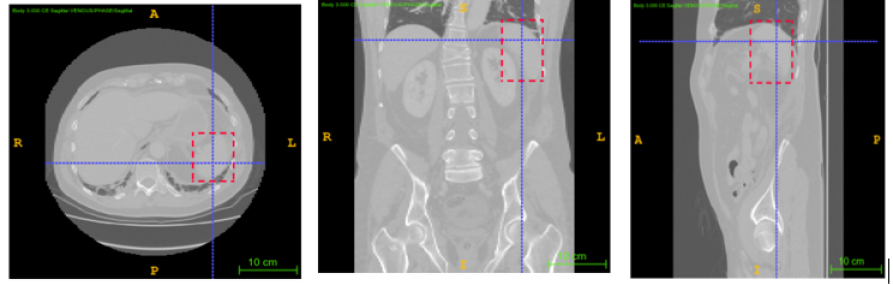

3.2.2 Annotation

The annotation process using ITK-SNAP in the three planes is illustrated in Fig 1 for creating a 3D bounding box around a lumbar spine region. The annotations of spleen, left and right kidneys are illustrated by Figures 2, 3 and 4 respectively.

The dataset was provided by the Prince of Wales Hospital, Randwick, NSW, Australia in an anonymised form after ethics approval (refer 3.1), and included 110 abdomen CT scans with a slice thickness of 3mm for lumbar spine and left kidney and 104 scans for spleen and right kidney localisation. The data set was manually annotated and verified by a radiologist with 10 years of experience, to identify the two diagonally opposite corner points of a 3D bounding box around the ROI. Annotations were performed to localise left and right kidneys using ITK-SNAP as described in section 3.2.2.